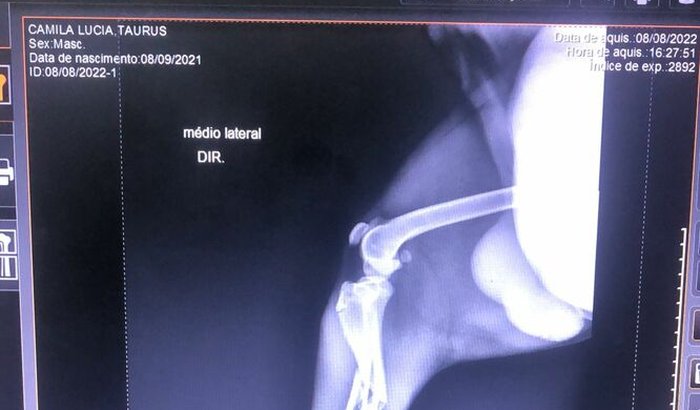

Eu sou leandro de freitas estou Precisando de uma ajuda de 2.810,00 para ajudar o tauros um cachorro de um amigo que foi atropelado e fraturou a pata no dia 07/08/2022 vamos juntos ajudar o tauros ver tudo

Eu sou leandro de freitas estou Precisando de uma ajuda de 2.810,00 para ajudar o tauros um cachorro de um amigo que foi atropelado e fraturou a pata no dia 07/08/2022 vamos juntos ajudar o tauros